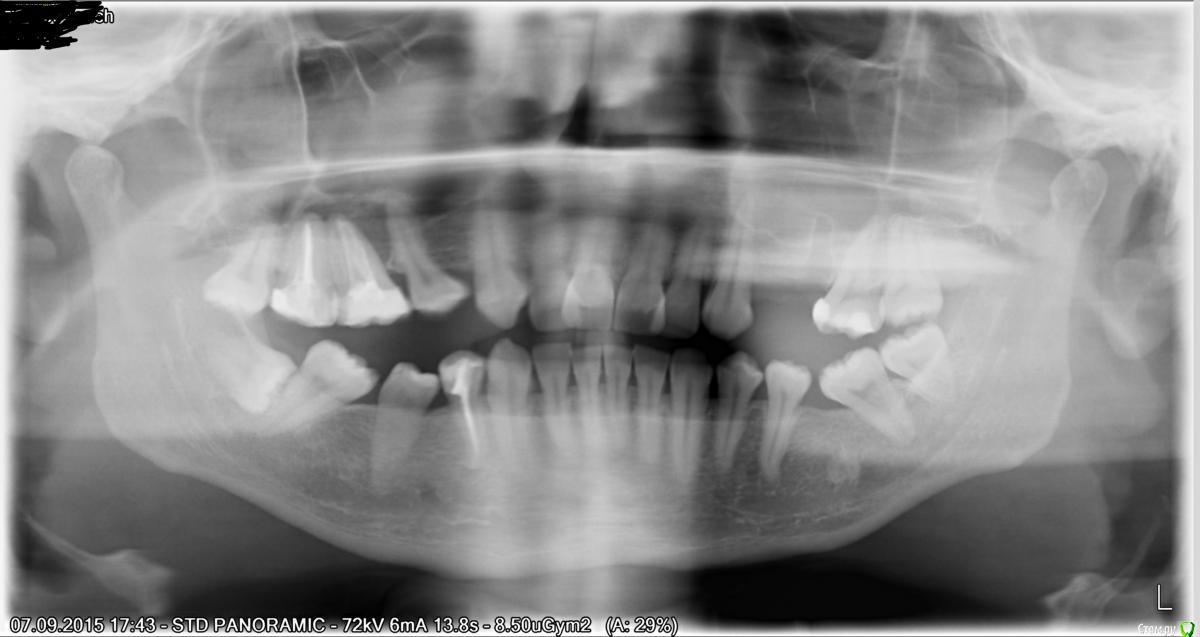

Ponchik Опубликовано 9 сентября, 2015 Поделиться Опубликовано 9 сентября, 2015 Добрый день. История следующая: я удалил 2.5 зуб и так как он был в проекции синуса ороантральное сообщение проверил, но щеки "дулись" исправно. Сгусток был какой-то маленький (ультракаин 1:200000), потому положил на уровне кортикалки "губку сплющенную ильгамовскую" и направляющие швы Викрил 5-0. Была среда.В понедельник смотрю пациента - швы на месте, ошметки губки частично тоже и реки гноя из лунки при просьбе подуть в зажатый нос. Со слов пациента заложенность носа и отделяемое из лунки появились еще в пятницу, но очень не когда было обратиться за помощью.Делаем ОПТГ, там конечно уровень в пазухе. Направляю пациента в стационар. Хотел бригадой скорой, но он отказался (письменно) и ушел сам, своим пешком.Сегодня. Звоню пациенту. Понедельник он в стационар не пошел(поздно было, а важностью момента пациент не проникся). Во вторник записался на прием в среду. И вот сегодня таки был у доктора. В стационаре сказали пить АБ дальше, пока воспаление не пройдет, а далее уже закрывать перфорацию (и вообще вдруг само закроется).Я по наивности думал, что будут проводить ревизию пазухи, закрывать перфорацию и несколько раз (в течении недельки скажем) промоют синус через со устье с носовым ходом.А тут наблюдение. Это нормальная тактика? Напоминает "открытый" зуб в терапии. Как вы ведете подобных пациентов? И еще вопрос как вы проверяете на ороантральное сообщение? Я так понимаю - перфорация была во время удаления, а проба ротоносовая была ложноотрицательной и я момент с перфо не определил. Может еще какой метод есть? ОПТГ после: Ссылка на комментарий